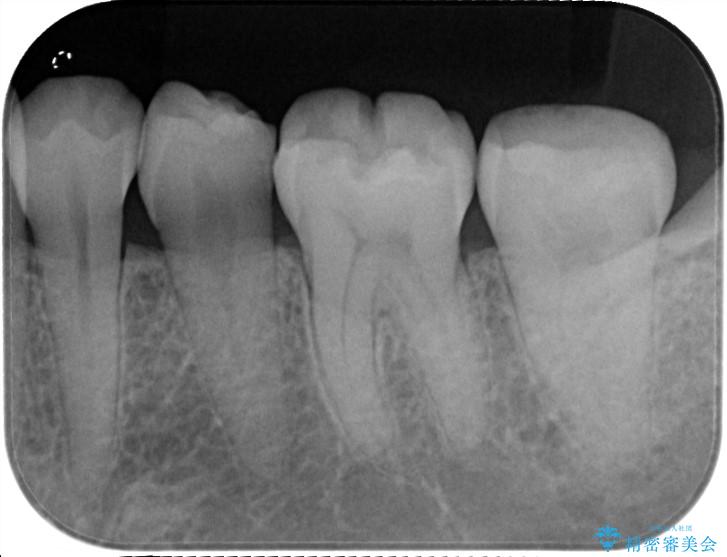

1つ目の医院にて詰め物による虫歯治療をしたところ、その後治療したはずの歯より痛みが発生。

2つ目の医院へ受診し検査してもらったところ、歯の根に膿があると診断され根管治療を2度ほど受けたが毎回の施術が15分程度であり、痛みが改善されず不安に感じ当院へ、ということでした。

検査をしたところ治療が必要と判断しましたので、症状改善のため根管治療をしてセラミッククラウンで修復治療を行うこととしました。